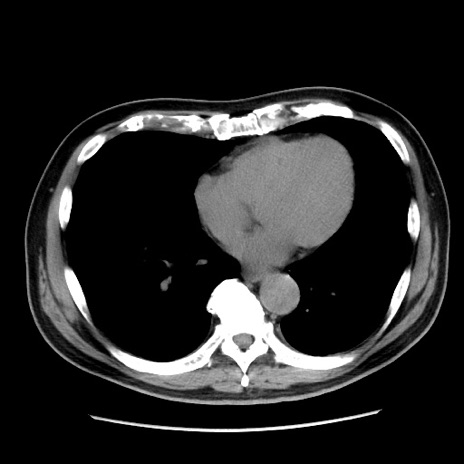

症例16(横断像)

【症例】 70歳代男性

【主訴】 腹痛、嘔吐

【現病歴】 約1ヶ月前より間欠的に腹痛と嘔吐あり、当院消化器内科を受診したところCTで多発する肝臓のLDAを指摘され、精査中であった。以降は消化器症状は安定していたが、2日前より嘔気と腹痛があり、同日より排便・排ガスが消失した。改善認めず、 本日、救急外来を受診した。

【既往歴】 大腸ポリープ切除後。

【身体所見】意識清明・会話良好、BT 36.3℃、BP 127/80mmHg、 P 80bpm、腹部:膨満あり、平坦・軟、上腹部正中および下腹部正中に圧痛あり、反跳痛なし、筋性防御なし。

【データ】WBC 7200、CRP 0.77